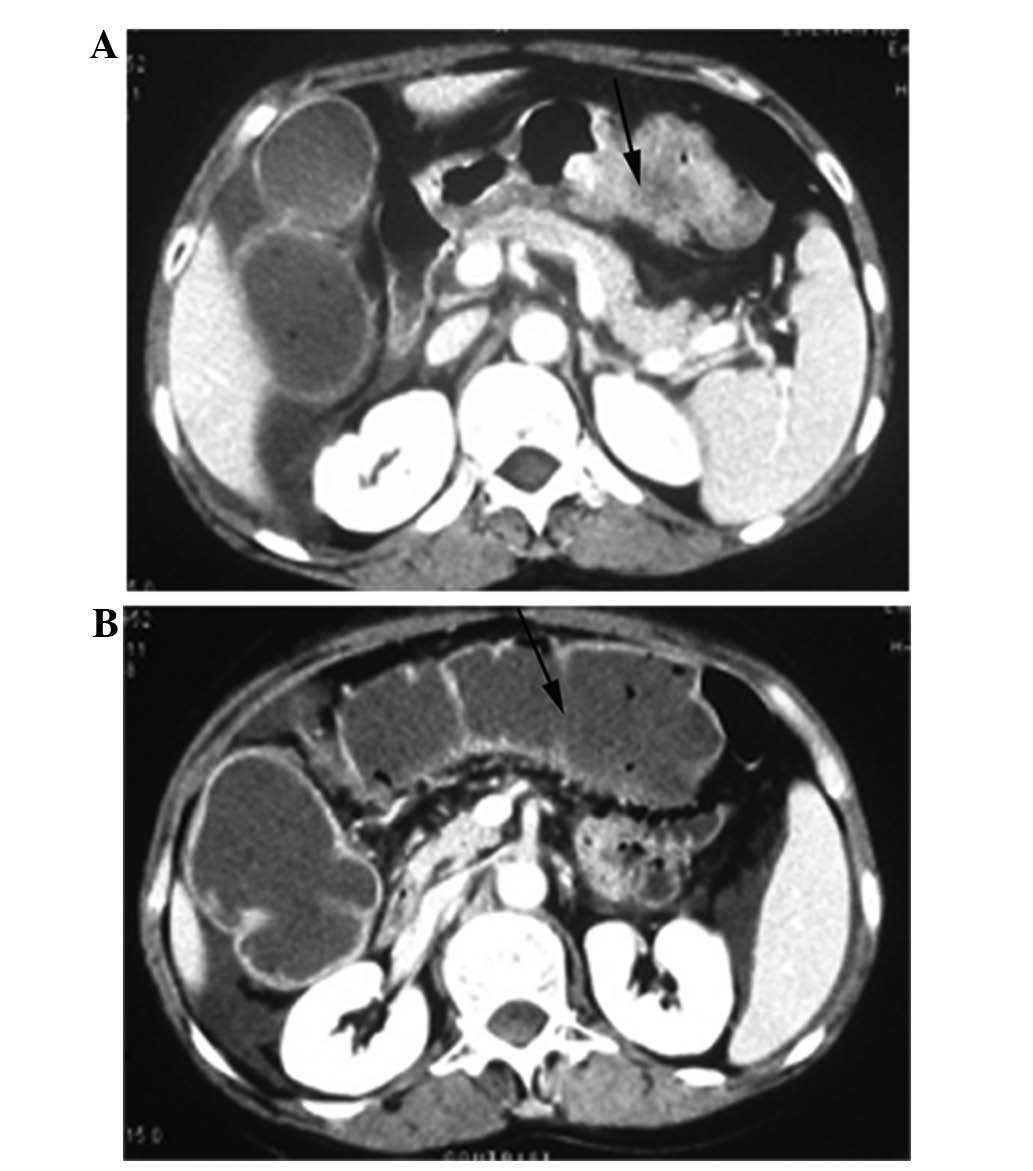

A 59-year-old female without no significant medical history visited Linan People’s Hospital (Hangzhou, China) complaining of central abdominal pain and not being able to defecate for 15 days. Although the patient had been admitted to Hangzhou Provincial Hospital due to recurrent abdominal pain six months previously, the colon was not considered abnormal following a colonoscopy and ultrasound. A gastroscopy only revealed chronic superficial gastritis (data not shown). Upon admittance to the Department of Surgery, the right epigastric region was slightly tender and active bowel sounds were identified, followed by intermittent bilious vomiting and weight loss, despite a distended abdomen without rebound pain or hepatomegaly. Computed tomography (CT) of the abdomen revealed a dilated fluid-filled colon and a protruding tumor abutting the transverse colon. No other abnormalities/metastases to the liver or the involvement of adjacent organs/tissues were observed (Fig. 1). An upper gastrointestinal endoscopy revealed the existence of a raised margin and thickening of the gastric mucosal in the antrum, with no evidence of ulcerative lesions (Fig. 2). The endoscopic gastric biopsies indicated a diagnosis of a poorly-differentiated adenocarcinoma. The routine blood test results were normal, with the exception of an elevated CA19-9 level (95 U/l; normal range, <39 U/l).

Figure 1

Computed tomography (CT) scan showing the gastric wall thickening and tumor infiltration into the (A) adjacent fat tissues and (B) colon, which were fluid-filled, indicative of a large bowel obstruction.

Although highly advanced stage gastric cancer often causes gastric outlet obstruction and results in gastrointestinal symptoms, including abdominal pain, nausea and vomiting, an acute large bowel obstruction as the first presentation of gastric cancer is a rare event. The main route of cancer infiltrating the abdominal organs is known as the diffusion of the adjacent tissues and the invasion of the superficial serosal layer (6). In the present study, the wall of the transverse colon was thickened on the CT and a poorly-differentiated adenocarcinoma was confirmed by the histology examination, revealing the true invasion from the primary gastric cancer. Gastroscopy indicated that the gastric mucosa was partly raised and the distant organs did not contain any lesions. However, the cancer cells invaded the adjacent tissues, suggesting that the biological behavior of cancer cells and the performance and progress of gastric cancer may vary.